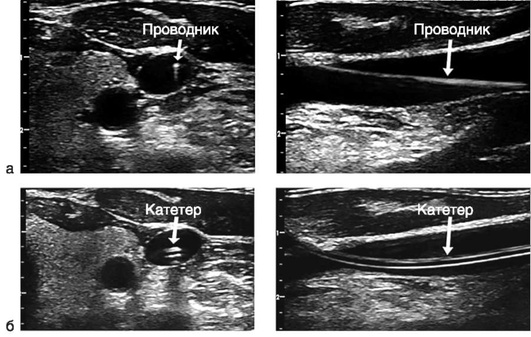

Катетеризация центральных вен

Показания к установке центрального венозного катетера (ЦВК).

ОСНОВНЫЕ ПОЛОЖЕНИЯ Выбор доступа